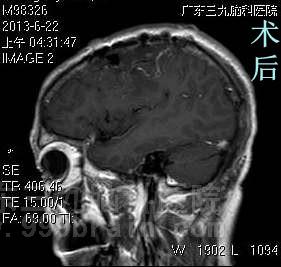

我院头颅MR检查提示左侧额顶部示一卵圆形占位性病变,大小约57.1*35.1*31.5mm.完善相关检查后,由综合神经外科鲁明主任主刀,在全麻下行左侧额顶部凸面脑膜瘤切除术,导航定位额部肿瘤投影区,纤维镜下见硬模下白色、质硬、边界清楚、无血供肿瘤组织,完整切除肿瘤,达辛普森I级切除,手术顺利结束。术后患者经专科治疗护理,术前症状好转,康复出院。术后病理结果:过渡型脑膜瘤,WHO I级。